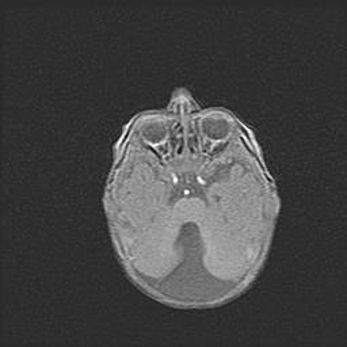

Неполная лизэнцефалия (пахигирия). Открытая гидроцефалия.

Возраст: 17 дней

Вес: 3110 г

Пол: мужской

Окружность головы: 33,5 см

Срок гестации: 35-36 недель

Лизэнцефалия—недоразвитие корковой пластинки и мозговых извилин в результате нарушения миграции нейронов коры. Поверхность мозговых полушарий гладкая. Микроскопически выявляется отсутствие нормальных слоев коры и скопление групп нейронов в подкорковом белом веществе.

Пахигирия—уменьшение числа вторичных извилин. В пораженном полушарии нервные клетки образуют толстый недифференцированный слой с неправильно расположенными нервными волокнами и группами гетеротопных клеток. Нервные клетки незрелые. Белое вещество истончено. При этом нередко аномально развит корково-спинномозговой путь.